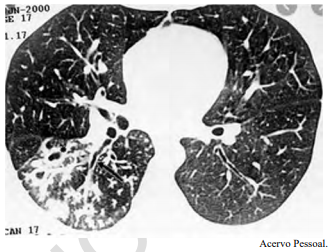

Um adolescente de 17 anos de idade procura atendimento em função de tosse vespertina, febre e hemoptise em pequena quantidade. Refere sudorese noturna e perda de peso. A tomografia de tórax apresenta nódulos centrolobulares com padrão de árvore em brotamento, além de pequenas cavitações espessas e de paredes irregulares, bem como brônquios espessados em segmento posterior do lobo inferior direito, conforme a imagem a seguir.

Tendo em vista esse caso clínico, a imagem apresentada e os conhecimentos médicos correlatos, julgue o item a seguir.

Tuberculose pulmonar é o diagnóstico provável.